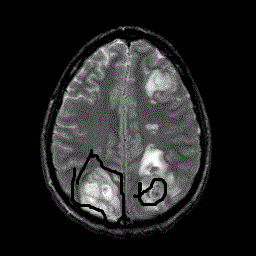

Опишите в каких внутричерепных структурах Вы нашли патологию (Саркома). Необходимо назвать отдел мозга.

вот я отметил посмотри